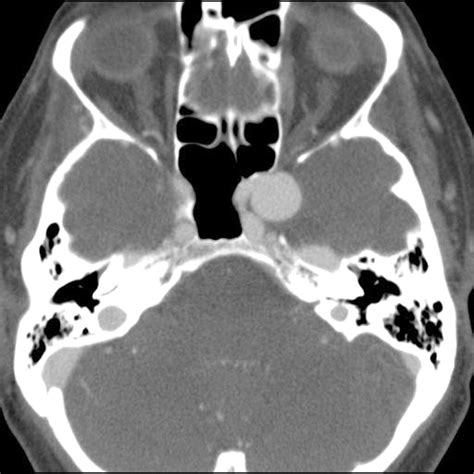

Diagnosing Cavernous Sinus Syndrome requires a high index of clinical suspicion and advanced imaging techniques. Physicians often utilize a combination of clinical evaluation and diagnostic testing to pinpoint the underlying etiology. Because the syndrome can be caused by various factors—from infections like sinusitis to malignant tumors or cavernous sinus thrombosis—the approach must be comprehensive.

CT Scan (Computed Tomography) Excellent for viewing bone involvement, particularly if the cause is related to paranasal sinus infection.

• Neoplasms: Pituitary adenomas, meningiomas, or metastatic tumors can exert pressure on the sinus walls.

• Vascular Issues: Carotid-cavernous fistulas or internal carotid artery aneurysms.